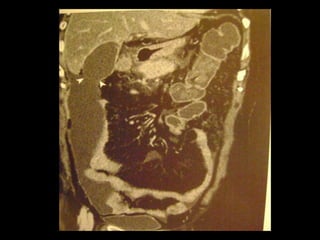

Colecistite Xantogranulomatosa

Na TC:

Os cálculos biliares e o espessamento irregular

semelhante a uma massa da parede da VB são as

anormalidades mais comuns.

Vários estudos relataram que os nódulos

hipoatenuantes intramurais vistos na TC

representam uma lesão xantogranulomatosa, um

abscesso ou a combinação de ambos;

Realce da superfície luminal(70%) correspondia à

presença de uma camada epitelial.

O radiologista deve distinguir entre a colecistite

xantogranulomatosa e o carcinoma da vesícula

biliar

Linha de mucosa evidente

Realce da superfície luminal

Nódulos intramurais hipoatenuantes(TC) ou com

sinal alto(RM T2)

http://radiographics.rsna.org/content/28/1/135.full